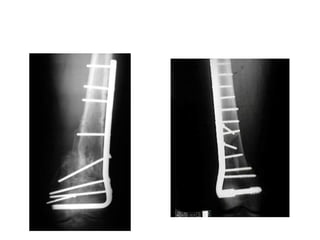

tibia fracture treated

locked IM Nail.

• Note the use of

multiple proximal

interlocks where

angular control is

more difficult to

maintain due to the

metaphyseal

flare.